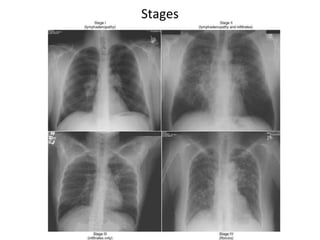

4 Stages of Pulmonary Sarcoidosis

I Bilateral hilar lymphadenopathy

and paratracheal adenopathy

55-90%

remission

II Mediastinal adenopathy with

pulmonary parenchymal

involvements

40-70%

III Pulmonary parenchymal without

adenopathy

10-20%

IV Pulmonary fibrosis with

honeycombing

0-5%

Stages